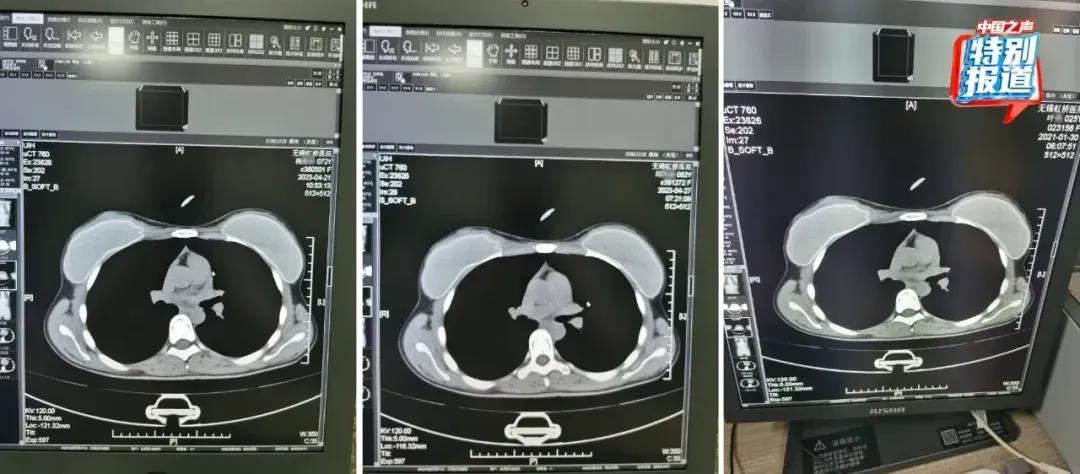

在被举报的病历中,杨某某(72岁)和邱某某(62岁)的病历里,有根据所拍片子的情况做出的诊断,却找不到对应的影像。6月份又查到了她们的CT影像,按照系统记录,这两人都是2023年4月做的胸部CT,片子上能清晰看出,两位患者的吊坠形状、大小和位置都基本一致。不仅这两位上了年纪的患者CT影像类似,朱医生比对发现,2021年在他们科做过CT的25岁女性叶某的片子上,也有看起来极为相似的吊坠,肉眼看,三人的片子几乎一模一样。

72岁的杨某某、62岁的邱某某与25岁的叶某,三人的片子几乎一模一样